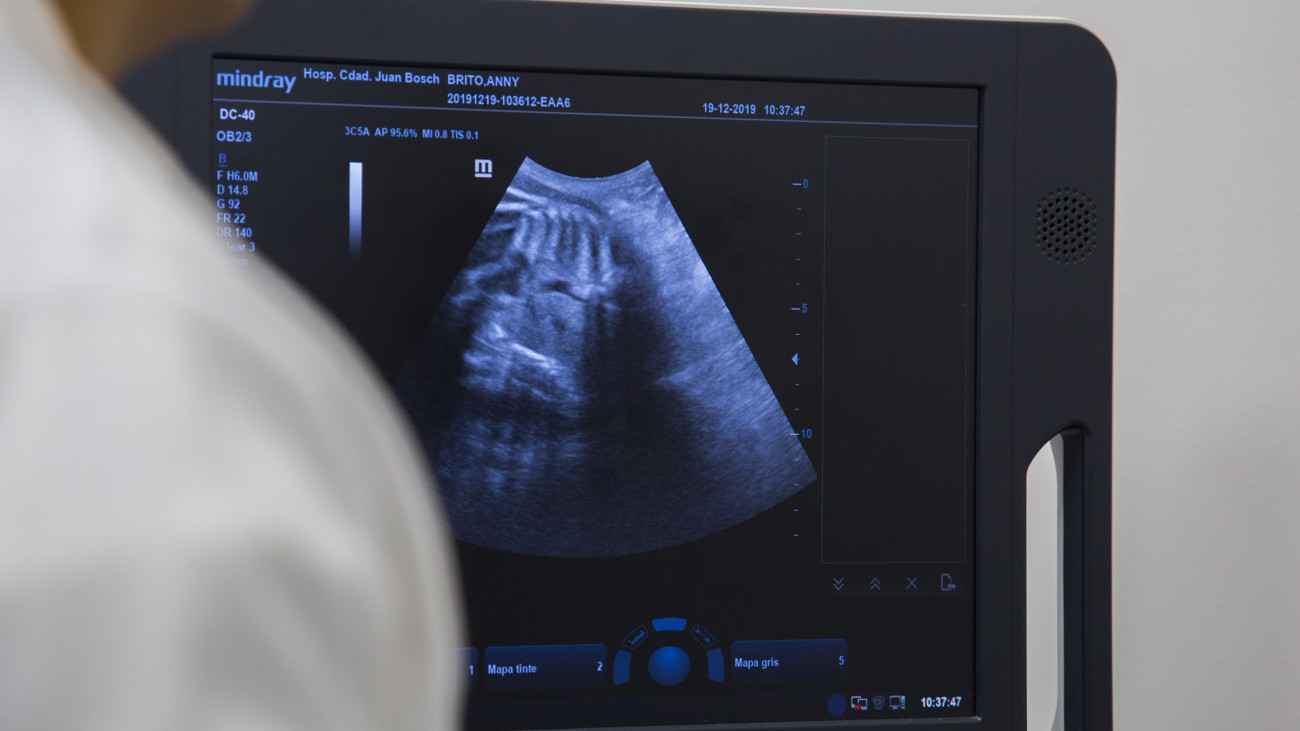

Las imágenes médicas sirven para un efectivo diagnóstico de la salud o enfermedad del paciente. Cuestan. El Hospital Ciudad Juan Bosch en Santo Domingo Este ofrece este servicio. ¿Qué opinan los pacientes?

Foto: José Ramón Cuevas Feliz